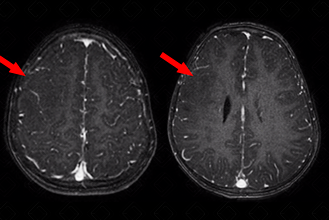

Texto alternativo para a imagem Figura 4. Créditos: Elazir Mota - Rio de Janeiro/RJ

Descrição da figura 4: Imagens axiais em T1 pós-contraste, do mesmo paciente, evidenciando discreta área hipointensa na mesma localização (setas vermelhas). Paciente com critérios para esclerose tuberosa; essa área de displasia cortical pode ser considerada um túber cortical.

• Túberes corticais: Essas lesões expansivas do SNC isoladamente não são diagnósticas de esclerose tuberosa, podendo ser observadas em outras patologias. Trata-se de hamartoma benigno presente no córtex de cerca de 95% dos pacientes com esclerose tuberosa. Esse tipo de alteração relaciona-se diretamente com as alterações e o quadro neurológico observado nesses doentes, incluindo epilepsia, distúrbios cognitivos e de comportamento. Caracterizam-se na ressonância magnética como lesões bem circunscritas, de baixo sinal em T1 e alto sinal em T2. Na maioria dos casos, a tomografia computadorizada do crânio falha na detecção dessas lesões ( figuras 3 e 4) ;